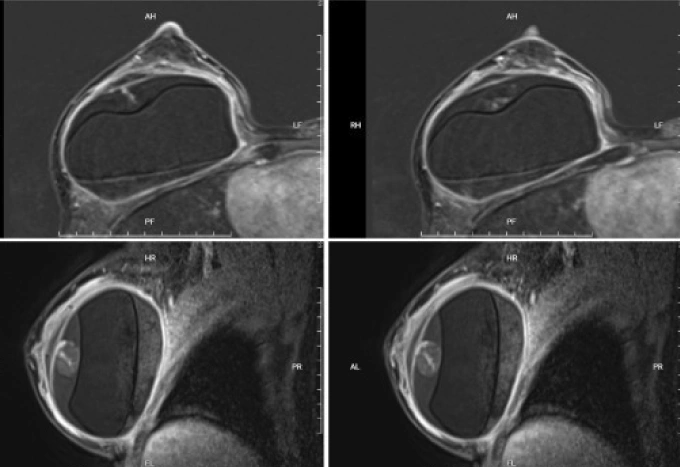

Tương tự, bà Thắm, 51 tuổi, đau ngực phải kéo dài, biến dạng ngực một bên. Bà cũng từng nâng ngực 10 năm trước. Khi đến Bệnh viện Đa khoa Tâm Anh TP HCM khám, ngực phải bà Thắm có dấu hiệu căng tức, biến dạng, bác sĩ nghi ngờ co thắt bao xơ túi ngực, vỡ túi ngực. Kết quả MRI phát hiện vỡ túi hai bên kèm tụ máu quanh, silicone rò ra mô xung quanh. Trong khi mổ, êkíp phẫu thuật hút khoảng 200 ml hỗn hợp máu và silicone, xử lý bao xơ, thay túi độn mới.

Hình MRI của bà Thắm cho thấy khối máu tụ bên trong ngực của bệnh nhân. Ảnh: Bệnh viện Đa khoa Tâm Anh